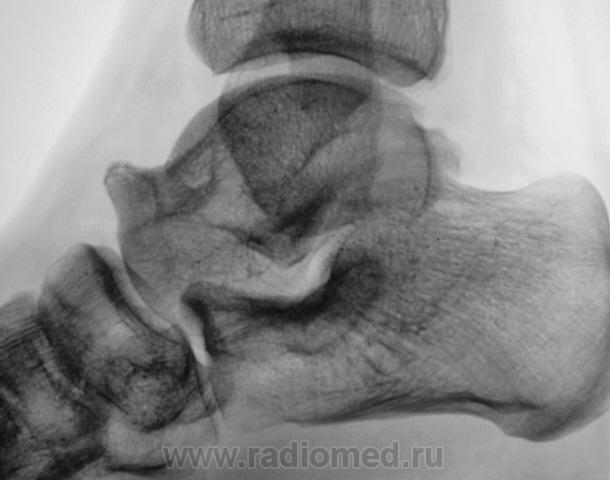

Пол пациента: Женский пол Тип патологии: Другое Область исследования: Другое Методы исследования: Rg Просто вопрос. Как можно рассматривать такую таранную кость? Гипертрофия, таран-гигант? https://radiomed.ru/sites/default/files/styles/case_slider_image/public/user/12/2.Gigant.jpg?itok=4HzRJNWV https://radiomed.ru/sites/default/files/styles/case_slider_image/public/user/12/3.Gigant..jpg?itok=HK478Gsj ID:3017 Thu, 15/04/2010 - 21:11 #1 Анатолий Владим... Offline Last seen: 7 years 11 months ago Joined: 16.10.2009 - 21:16 Posts: 1941 Вариант развития таранной кости, а насчет сапогов и венкомата не знаю... Thu, 15/04/2010 - 21:17 #2 Катенёв Валенти... Offline Last seen: 7 years 2 months ago Joined: 22.03.2008 - 22:15 Posts: 54876 Здравствуйте Анатолий Владимирович! Нет, это не военкомат. Если-бы был военкомат, то был-бы явно не годен не благодаря самой таранной кости, а той "стоялке", что по передне-верхнему краю таранной кости. Thu, 15/04/2010 - 21:23 #3 Almo Offline Last seen: 13 hours 49 min ago Joined: 28.09.2008 - 18:50 Posts: 8282 Поддерживаю пост Анатолия Владимировича-вариант развития таранной кости. Thu, 15/04/2010 - 21:46 #4 Катенёв Валенти... Offline Last seen: 7 years 2 months ago Joined: 22.03.2008 - 22:15 Posts: 54876 Как расценивать такое положение головки плечевой кости и состояние ключично-акромиального сочленения? Приложения: Thu, 15/04/2010 - 21:58 #5 Анатолий Владим... Offline Last seen: 7 years 11 months ago Joined: 16.10.2009 - 21:16 Posts: 1941 Вероятно врожденная деформация... Thu, 15/04/2010 - 21:58 #6 Катенёв Валенти... Offline Last seen: 7 years 2 months ago Joined: 22.03.2008 - 22:15 Posts: 54876 Это я решил попробовать Вашу идею, Анатолий Владимирович, "с учетом одного снимка" Thu, 15/04/2010 - 22:01 #7 Анатолий Владим... Offline Last seen: 7 years 11 months ago Joined: 16.10.2009 - 21:16 Posts: 1941 Здравствуйте Валентин Львович! Может это приживется.... Thu, 15/04/2010 - 22:13 #8 Катенёв Валенти... Offline Last seen: 7 years 2 months ago Joined: 22.03.2008 - 22:15 Posts: 54876 Будем надеяться.

Вариант развития таранной кости, а насчет сапогов и венкомата не знаю...

Нет, это не военкомат. Если-бы был военкомат, то был-бы явно не годен не благодаря самой таранной кости, а той "стоялке", что по передне-верхнему краю таранной кости.

Поддерживаю пост Анатолия Владимировича-вариант развития таранной кости.